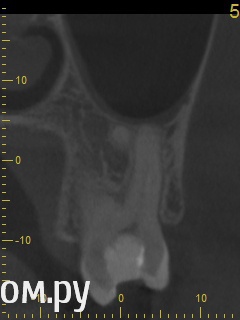

Анатолий М Опубликовано 21 апреля, 2014 Поделиться Опубликовано 21 апреля, 2014 Добрый день. Помогите пожалуйста.17 зуб (верхняя семерка с права). Пол года назад был депульпирован. Все это время присутствуют боли под этим зубом по симптомам очень похожие на кисту (распирание, боль ноющая не сильная, то появляется то сама собой изчезает. при перкуссии 17 зуб слегка болезненный). 2 месяца наза решили зуб перелечить. На ОПТГ ситуация до перелечивания. По снимку видно что первоначальное лечение было проведено плохо. Корни были плохо пройдены и плохо заполены цементом.Месяц хождения с гидроокисью кальция на воде никакого эфекта не дали. Врачи считают что под зубом есть киста. И предлагают удалить зуб. Так как перелечивание не помогло.Прилагаю снимок КЛКТ после лечения. Зуб все еще под временной пломбой. Из трех врачей лишь один разгледел на КЛКТ кисту под 17 зубом. Два других ни на КЛКТ ни на прицельных никакой кисты не видят. Направили к неврологу. Думают что киста если она и есть (в чем они не уверены) не дает имеющихся симптомов.Пожалуйста посмотрите на КЛКТ. Есть ли там киста или нет? И могут ли боли быть от нее?Заранее спасибо. Ссылка на комментарий

Анатолий М Опубликовано 21 апреля, 2014 Автор Поделиться Опубликовано 21 апреля, 2014 Снимок во время лечения делали? Коффердам и оптика использовались? На кт в тех срезах что Вы выложили кисты не вижу Снимки во время лечения делали три раза прицельные с иголками в каналах. Но они остались у врача. У меня их нет. Но она по ним кисты не видела. Коффердам использовали только при первом посещении когда вскрывали старую пломбу и прорабатывали каналы. При последующих посещениях при смене лекарст его не использовали так как кольцо на зубе плохо держалось и постоянно слетало. Плюс травмировало десну.Микроскоп использовали все три раза. По словам врача (врач высшей категории эндодонтист зав отделением):При вскрытии старой пломбы каналы практически не заполены цементирующим составом. Иструмент при вскрытии пломбы в каналы проваливался. Хотя стояла постоянна пломба. Из трех каналов лишь один был проработан до верхушки корня. Два других либо до половины либо на треть. Врачь полностью прошла все каналы и даже залезла за апекс. туда при первом пломбировании врач даже не пыталась лезть. При третьем посещении врач констатировала что каналы чистые. Никаких признаков инфекции нет. И белезненная перкуссия от чего то другого. Специально проводила ревизию каналов при втором и третьем посещении без анастезии что бы понять где болит. Но так и не поняла. Повела на консультацию к профессору в их стоматологи. Посмотрев контрольную КТ он сказал что там киста и надо удалять зуб! Похоже что мой врач с ним не очень согласна, хотя и спорить не стала поэтому отправила меня на консультацию к неврологу. Ниже срезы конрольного КТ после месяца лечения гидрооксидом кальция на воде. Срезы по дуге. Сделал как смог. Шаг срезов как я понимаю 1мм. Линия по перек дуги снимок номер 1 (см нумерацию в конце названия файла) Ссылка на комментарий

igorstom Опубликовано 26 апреля, 2014 Поделиться Опубликовано 26 апреля, 2014 (изменено) Понятие кисты двоякое. Кистой можно назвать полостное образование размером на рентгеновском снимке более 8 мм в диаметре. Ну а есть понятие гистологическое. Тут размер не имеет значения. А результаты гистологического исследования - эпителиальная выстилка и клеточные элементы. В практике, по крайней мере у нас на Урале доктора часто "кистами" называют даже незначительные округлые элементы на верхушках корней. Так что причин на мой взгляд для беспокойства нет. А вот пустота каналов лично меня насторожила бы. Гидроокись кальция всё-таки рентгеноконтрастна, хоть и незначительно. Но и этого я не увидел на снимках. Но это только моё вИдение. Изменено 26 апреля, 2014 пользователем igorstom 1 Ссылка на комментарий